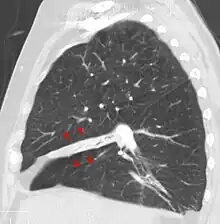

Clinically significant atelectasis is generally visible on chest X-ray; findings can include lung opacification and/or loss of lung volume. Post-surgical atelectasis will be bibasal in pattern. Chest CT or bronchoscopy may be necessary if the cause of atelectasis is not clinically apparent. Direct signs of atelectasis include displacement of interlobar fissures and mobile structures within the thorax, overinflation of the unaffected ipsilateral lobe or contralateral lung, and opacification of the collapsed lobe. In addition to clinically significant findings on chest X-rays, patients may present with indirect signs and symptoms such as elevation of the diaphragm, shifting of the trachea, heart and mediastinum; displacement of the hilus and shifting granulomas.[11]

In rounded atelectasis (folded lung or Blesovsky syndrome[18]), an outer portion of the lung slowly collapses as a result of scarring and shrinkage of the membrane layers covering the lungs (pleura), which would show as visceral pleural thickening and entrapment of lung tissue. This produces a rounded appearance on X-ray that doctors may mistake for a tumor. Rounded atelectasis is usually a complication of asbestos-induced disease of the pleura, but it may also result from other types of chronic scarring and thickening of the pleura.